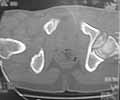

Male 22 yrs of age, RTA, front seat passenger in a truck. Sustained grade IIIB fracture of Tibia, and a Posterior dislocation of the Ipsilateral Left Hip.

Emergent closed reduction performed, and Tibial wound debrided. Next day Exfix applied and fibula plated. Initially femoral head fracture was not appreciated and it was thought that this is a posterior wall fracture. Presently two weeks down the line, Tibial wound is better but not completely healthy. and plastics want to wait for another five days, before they flap it. I enclose radiographs, Judet view, Ct scans in this and following mails.

2)The femoral head fracture involves the anter-inferior part and not the weight bearing superior dome. Also while moving the hip after taking weight off the traction, it does seem pretty stable. Should it be fixed even then?

Based on the selected images that you shared with us, I would not leave it as is. The fragment is significant in terms of its size and location and displacement.